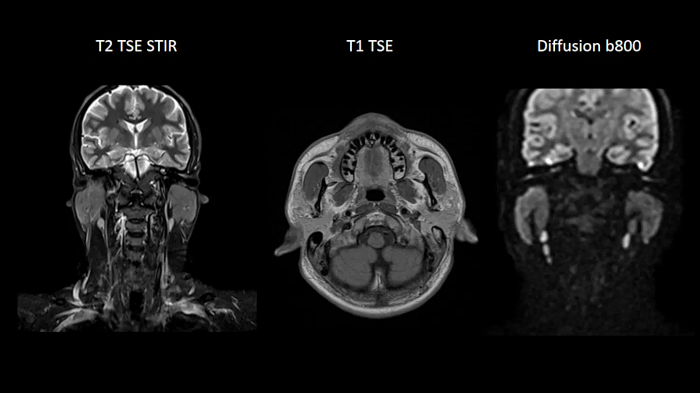

Neck

Excellent soft tissue contrast in the neck

An all-inclusive soft tissue investigation in the head with outstanding image quality for T1, T2, and diffusion contrast.

MAC-ID: 7aaaa0158.

MAC-ID: 7aaaa0158. Image Credit: Siemens Healthineers